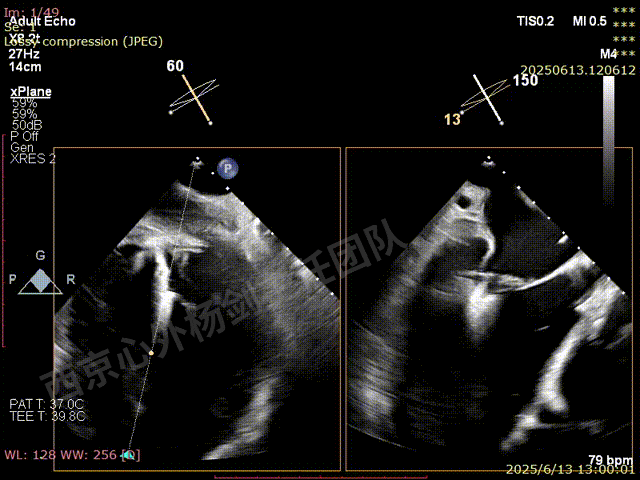

二尖瓣后叶栓系严重,前叶相对错位,反流束沿2区分布广泛,2偏3区处存在反流。

反流宽度至少23mm,因影像调整困难,考虑实际反流更宽。